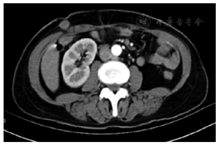

5例均在术前行腹部增强CT和MR排除腹腔及远处转移后行手术切除,术后恢复良好,无切口感染和切口疝发生。腹腔镜胃癌根治术大多采用"五孔法",各个穿刺孔都有可能发生种植转移。肿瘤位于皮下组织2例、肌层1例、脐部穿刺孔处2例(图1,图2,图3)。